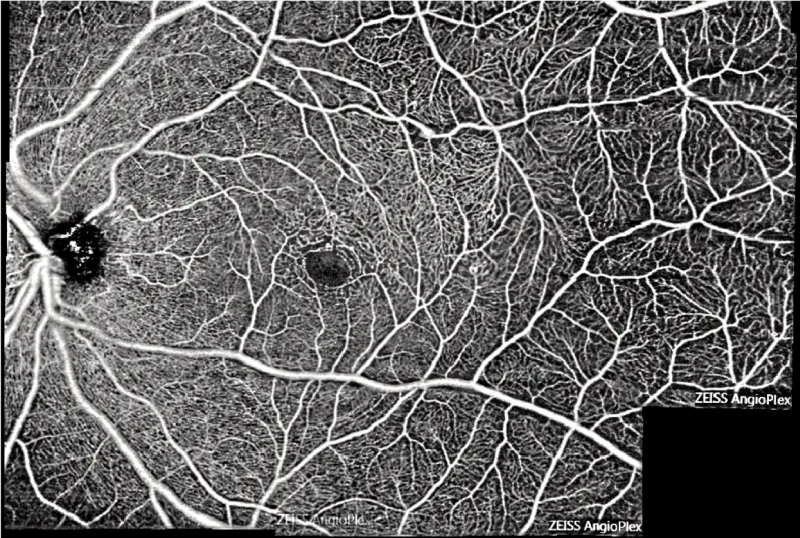

Examen d'OCT-Angiographie du même patient permettant d'imager le flux intravasculaire et mettant en évidence de nombreuses dilatations des capillaires intra-rétinien dans la région temporo-fovéolaire dans le cadre d'une maladie de Coats